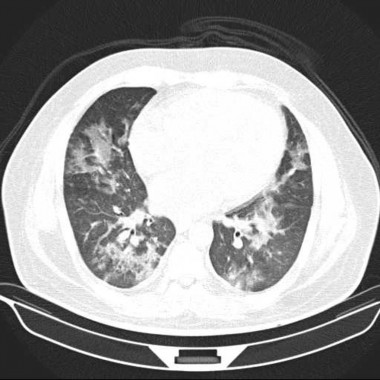

Case courtesy of Dr Mohammad Taghi Niknejad, Radiopaedia.org. From the case rID: 21347